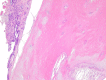

Otosclerosis is a bone condition affecting the stapes bone within the otic capsule, and its exact cause is still unknown. It is characterized by a lack of proper remodeling of newly formed vascular and woven bone, leading to the development of abnormal osteons and the formation of sclerotic bone. Bilateral otosclerosis is seen in 80% of patients and 60% of otosclerosis patients have a family history of the condition. The etiology of this disease is still unknown, there are lots of theories to explain it. The histopathological (HP) studies of otosclerosis showed that osteoblasts, osteoclasts, vascular proliferation, fibroblasts, and histiocytes were observed in the stapes footplate. The onset of the symptoms occurs by the early third decade of life, usually it doesn't start later. In otosclerosis, the energy exerted by sound at the level of the tympanic membrane is reduced in the inner ear due to the fixation and rigidity of the ossicular chain, leading to hearing loss, especially for low frequencies. The primary clinical symptom of otosclerosis is conductive hearing loss but it is important to note that sensorineural hearing loss and mixed hearing loss can also occur as secondary symptoms of the condition. Another symptom present in patients with otosclerosis is tinnitus. The paper carried out a retrospective study of 70 patients diagnosed with otosclerosis in the Department of Otorhinolaryngology of Emergency City Hospital, Timişoara, Romania, between January 2021 to December 2022. Tissue fragments were processed at Service of Pathology by standard Hematoxylin-Eosin staining. The HP diagnosis was completed using Masson's trichrome staining, Giemsa histochemical staining, and immunohistochemical (IHC) reactions with anti-cluster of differentiation (CD)20, anti-CD3, anti-CD4, anti-CD8, anti-CD34, and anti-CD31 antibodies. The microscopic examination showed a chronic diffuse inflammatory infiltrate that consisted predominantly of mature T-lymphocytes, immunohistochemically positive for CD3, CD4 and CD8. There were also present rare CD20-positive B-lymphocytes. Among the lymphocytes, relatively numerous mast cells were identified, highlighted histochemically by the Giemsa staining. They had numerous purple-violet intracytoplasmic granules. In the connective tissue support, a relatively rich vascular network was identified, consisting of hyperemic capillaries, highlighted immunohistochemically with anti-CD31 and anti-CD34 antibodies. Bone tissues trabeculae showed extensive areas of fibrosis. The collagen fibers were highlighted by Masson's trichrome staining, being stained in green, blue, or bluish green.